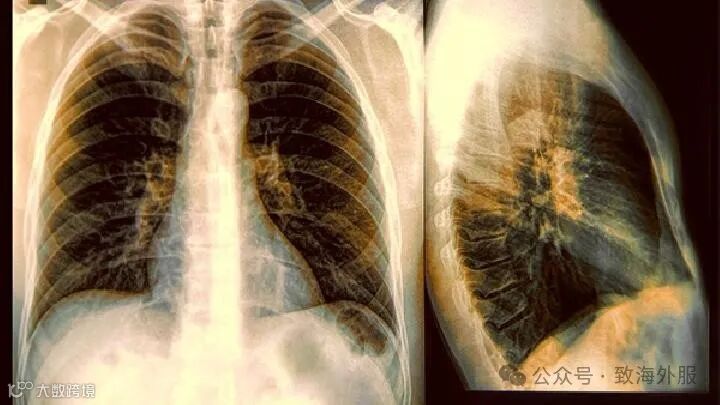

3.得了间质性肺炎时要及时去治疗,否则会让疾病越来越严重,在临床上,有的间质性肺炎患者会出现刺激性咳嗽,有少数患者会出现发烧症状,严重者会伴有咳血或胸痛等症状。通过肺部DR片和CT应该能够确诊。